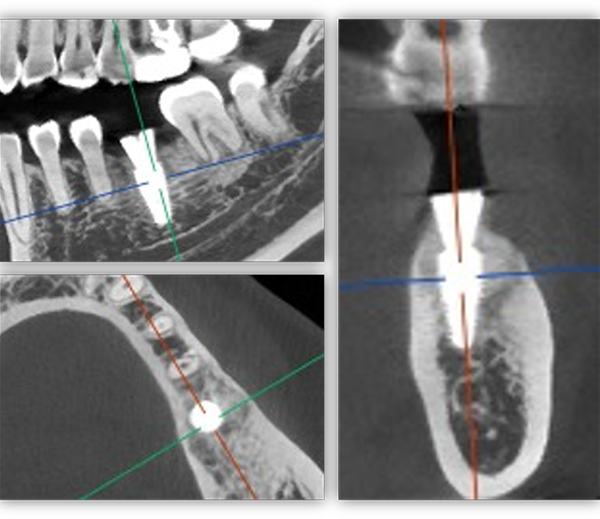

为满足患者的需求,我为她制订了一个即拔即种、种植后早期负重的方案,把五个治疗步骤缩减为三步。首次来院时,我为她完成了拔牙、种牙和安装基台,6周后来院拆线和取模,两周后完成牙冠修复,也就是戴牙。整个治疗周期仅8周,不到两个月就完成了。

6号牙也就是第一磨牙,是最早萌出的恒牙,比较容易龋坏。它虽然不在前牙美学区,不太容易影响容貌,但出于对美学的高要求,我在设计方案时也考虑了是按常规流程先拔牙,再备洞,还是以修复为导向,先按现有的牙冠来确定未来修复体的形状,再去反推种植体植入的位置。后者对医生来说难度更高一些,但更有利于复原天然牙的形态。

为保证这个方案的顺利实施,我通过查阅文献去印证方案的可行性,还为她建议了适合的种植体,原来三个月的骨结合时间能缩短为两个月,种植体功不可没。